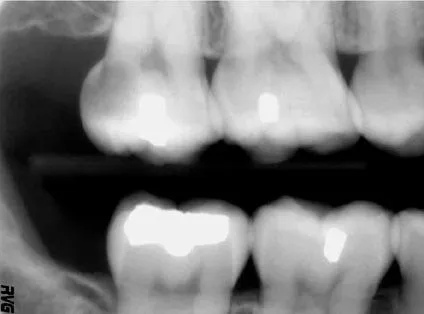

Digital radiography (digital X-ray) is the latest technology used to take dental X-rays.  This technique uses an electronic sensor (instead of X-ray film) that captures and stores the digital image on a computer.  This image can be instantly viewed and enlarged, helping the dentist and dental hygienist detect problems more easily.  Digital X-rays reduce radiation 80-90% compared to the already low exposure of traditional dental X-rays.

Dental X-rays are essential, preventative, diagnostic tools that provide valuable information not visible during a regular dental exam.  Dentists and dental hygienists use this information to safely and accurately detect hidden dental abnormalities and complete an accurate treatment plan.  Without X-rays, problem areas can go undetected.

Dental X-rays may reveal:

• Abscesses or cysts.

• Bone loss.

• Cancerous and non-cancerous tumors.

• Decay between the teeth.

• Developmental abnormalities.

• Poor tooth and root positions.

• Problems inside a tooth or below the gum line.

Detecting and treating dental problems at an early stage can save you time, money, unnecessary discomfort, and your teeth!

A full mouth series of dental X-rays is recommended for new patients.  A full series is usually good for three to five years.  Bite-wing X-rays (X-rays of top and bottom teeth biting together) are taken at recall (check-up) visits and are recommended once or twice a year to detect new dental problems.